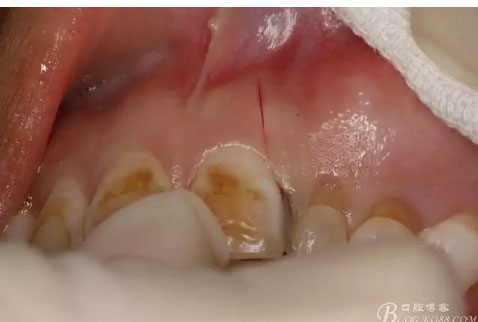

圖2.術前口內像,左側乳Ⅱ、Ⅲ滯留,頸部楔形缺損,探針不敏感。左側乳Ⅱ、Ⅲ唇側粘膜膨隆,表面結節(jié)狀,捫診質地堅硬,無波動。

圖7.行左側乳Ⅱ近中唇側垂直切口,切透粘骨膜。

圖8. 沿左側乳Ⅱ、Ⅲ唇側齦溝內切口至24部位。